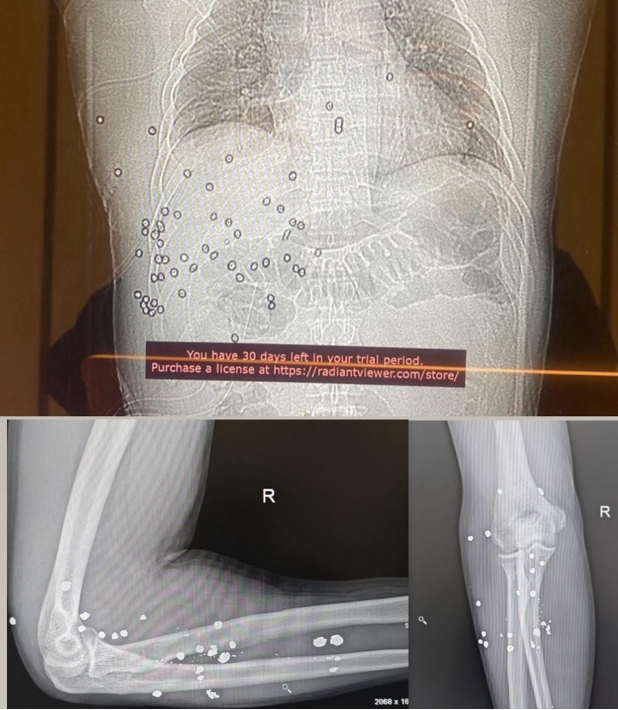

Берденовтың сөзінше, қазір оның денесінде әлі 60-тан астам қорғасын оқ бар.

фото: Руслан Берденовтың Facebook парақшасынан